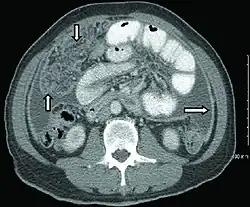

Chest X-ray and CT

In active pulmonary TB, infiltrates or consolidations and/or cavities are often seen in the upper lungs with or without mediastinal or hilar lymphadenopathy or pleural effusions ( tuberculous pleurisy). However, lesions may appear anywhere in the lungs. In disseminated TB a pattern of many tiny nodules throughout the lung fields is common - the so-called miliary TB. In HIV and other immunosuppressed persons, any abnormality may indicate TB or the chest X-ray may even appear entirely normal.

Abnormalities on chest radiographs may be suggestive of, but are not necessarily diagnostic of, TB. However, chest radiographs may be used to rule out the possibility of pulmonary TB in a person who has a positive reaction to the tuberculin skin test and no symptoms of the disease.

Cavitation or consolidation of the apexes of the upper lobes of the lung or the tree-in-bud sign[15] may be visible on an affected patient's chest X-ray.[1] The tree-in-bud sign may appear on the chest CTs of some patients affected by tuberculosis, but it is not specific to tuberculosis.[15]